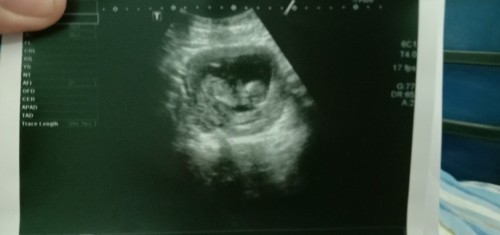

สอบถาม13สัปดาห์

ขอสอบถาม 13สัปดาห์แล้วน้องยังไม่เป็นตัว คนอื่นเป็นเหมือนกันไหมคะ แต่หมอบอกหัวใจน้องเต้น กังวลคะ จะเป็นไรไหม

นี่12สัปดาห์คะท้องแรกเห็นชัดเลยคะ

12 สัปดาห์ค่ะ น้องเป็นตัวแล้วนะคะ

ซาวครั้งแรก 13week เป็นตัวแล้วค่ะ

13สัปดาห์ห์เห็นตัวเเล้วจร้า